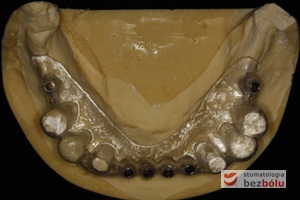

Gotowy most z maską dziąsłową - zastosowanie maski dziąsłowej uzasadnione długością zębów

Gotowy most z maską dziąsłową – zastosowanie maski dziąsłowej uzasadnione długością zębów